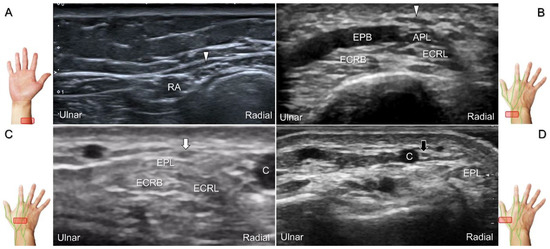

Scanning Technique

With the forearm supinated, the transducer is positioned in the axial plane at the lateral aspect of the antecubital fossa. The superficial and deep radial nerves are situated between the brachioradialis and brachialis muscles. The superficial radial nerve initially courses next to the radial artery below the brachioradialis muscle, and then departs from the radial artery in the distal third of the forearm (Figure 21A). Distally, it pierces the antebrachial fascia between the extensor carpi radialis longus and brachioradialis tendons. When tracking the terminal portion of the superficial radial nerve, the forearm can be pronated, as it courses toward the dorsal radial aspect of the wrist/hand. The superficial radial nerve travels above the proximal intersection junction between the first and second dorsal extensor compartments (Figure 21B). Later, it divides into the dorsomedial and dorsolateral branches. The former courses above the distal intersection junction of the second and third compartments (Figure 21C). The latter runs beside the extensor pollicis longus tendon (Figure 21D).

Figure 21. Sonographic imaging (short-axis view) of the superficial radial nerve from the distal third of the supinated forearm (A). With the pronated forearm, the nerve is seen to travel above the proximal intersection junction (B), divide into the dorsomedial branch coursing above the distal intersection junction (C), and the dorsolateral branch running beside the extensor pollicis longus tendon (D). Arrowheads: superficial radial nerve; white arrow: dorsomedial branch; black arrow: dorsolateral branch. RA: radial artery; APL: abductor pollicis longus tendon; EPB: extensor pollicis brevis tendon; ECRL: extensor carpi radialis longus tendon; ECRB: extensor carpi radialis brevis tendon; EPL: extensor pollicis longus tendon; C: cephalic vein.